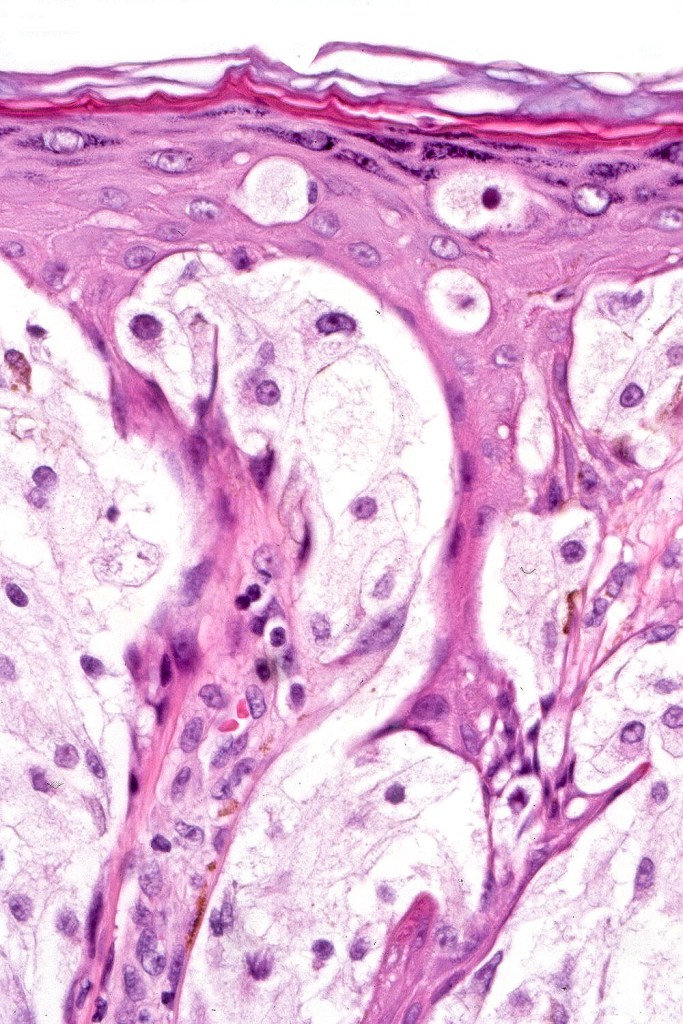

•Enlarged cells with copious eosinophilic, foamy or clear cytoplasm (some authors include melanoma with clear cell change in the same category)

•Variable pigmentation

•Nuclei vesicular or hyperchromatic

•Pleomorphism is not generally marked and indeed can be very subtle

•DPAS granules

•Thought to be a result of abnormal or degenerative melanosome change